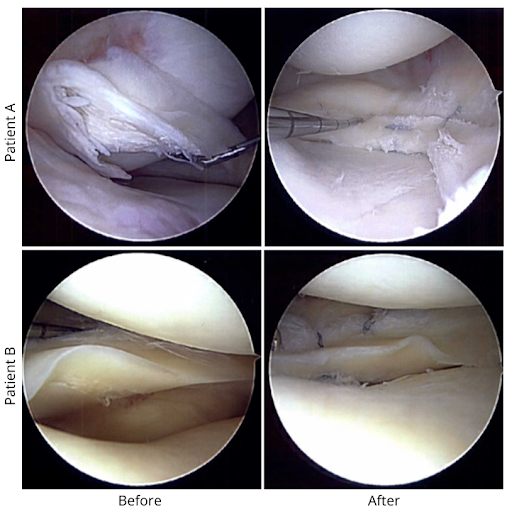

• Meniscus repair (stitching the meniscus together) preserves tissue and helps long-term knee health, but recovery is longer (often 4–6+ months).

• Partial meniscectomy (removal of torn tissue) returns quicker (6–10 weeks), but increases long-term arthritis risk.